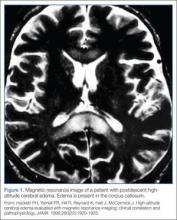

The exact mechanism of HACE is unclear. Magnetic resonance imaging of patients with the condition demonstrates cerebral edema primarily localized to the corpus callosum.11 These findings suggest an increased permeability in the blood-brain barrier, leading to vasogenic cerebral edema. Cases of death associated with HACE are the result of herniation. Fortunately, if the condition is recognized promptly and appropriate management is instituted, most patients will recover without permanent deficits.